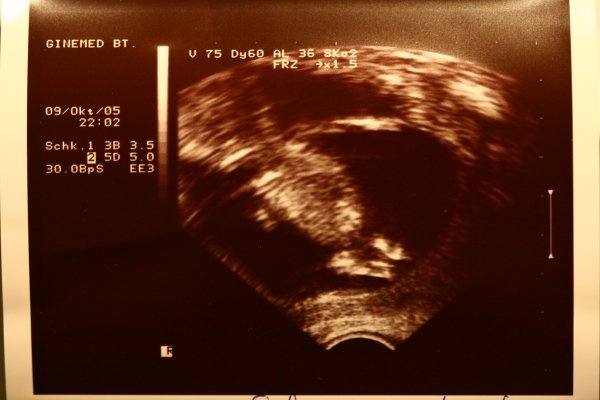

Nem tudom a méreteket, mert elfelejtettük megmérni. :lol: De majd holnap a Péterfy-ben jól megmérik mindenét! :lol: Látszólag minden rendben. Már amit lehet ezzel a gagyi kis UH-gal látni. Jól érzi magát, a kis lábaival fellöki magát, hadonászik a kezével. Úszkál vagy vezényel... ez nem derült ki. :lol: Vizelet rendben, méhszáj zárt. Nincs hasűri folyadék.

Gyönyörűséges a Babád! :lol: És gratulálok a 12. héthez! :lol:

Szépen kivehető, hogy mi hol van a kis csibésznek!

A gépen elfelejtették beállítani a dátumot? vagy az a szülés várható ideje a baloldal közepén? időpontra pontosan? :lol:

Hajnoca, igen, nincs beállítva a dátum a gépen. :lol:

Skrisz,ez szuper :D kezek-lábak,tényleg nagyon jól láttszik minden :D :D :D gratula :D hüvelyi uhu volt?

Hajnoca, augusztus 1. ha minden igaz.

Nyulasz, igen hüvelyi volt.

Skrisz: gratula a 12-höz! :-) mekkora már a babád!!! Úszóbajnok lesz vagy karmester ezek szerint :-D vagy szinkronúszó, esetleg vízilabdázó :-D Ma is hozol képet?

Szezso, nekem is minden este lufi. :lol: Naná, hogy hozok képet!